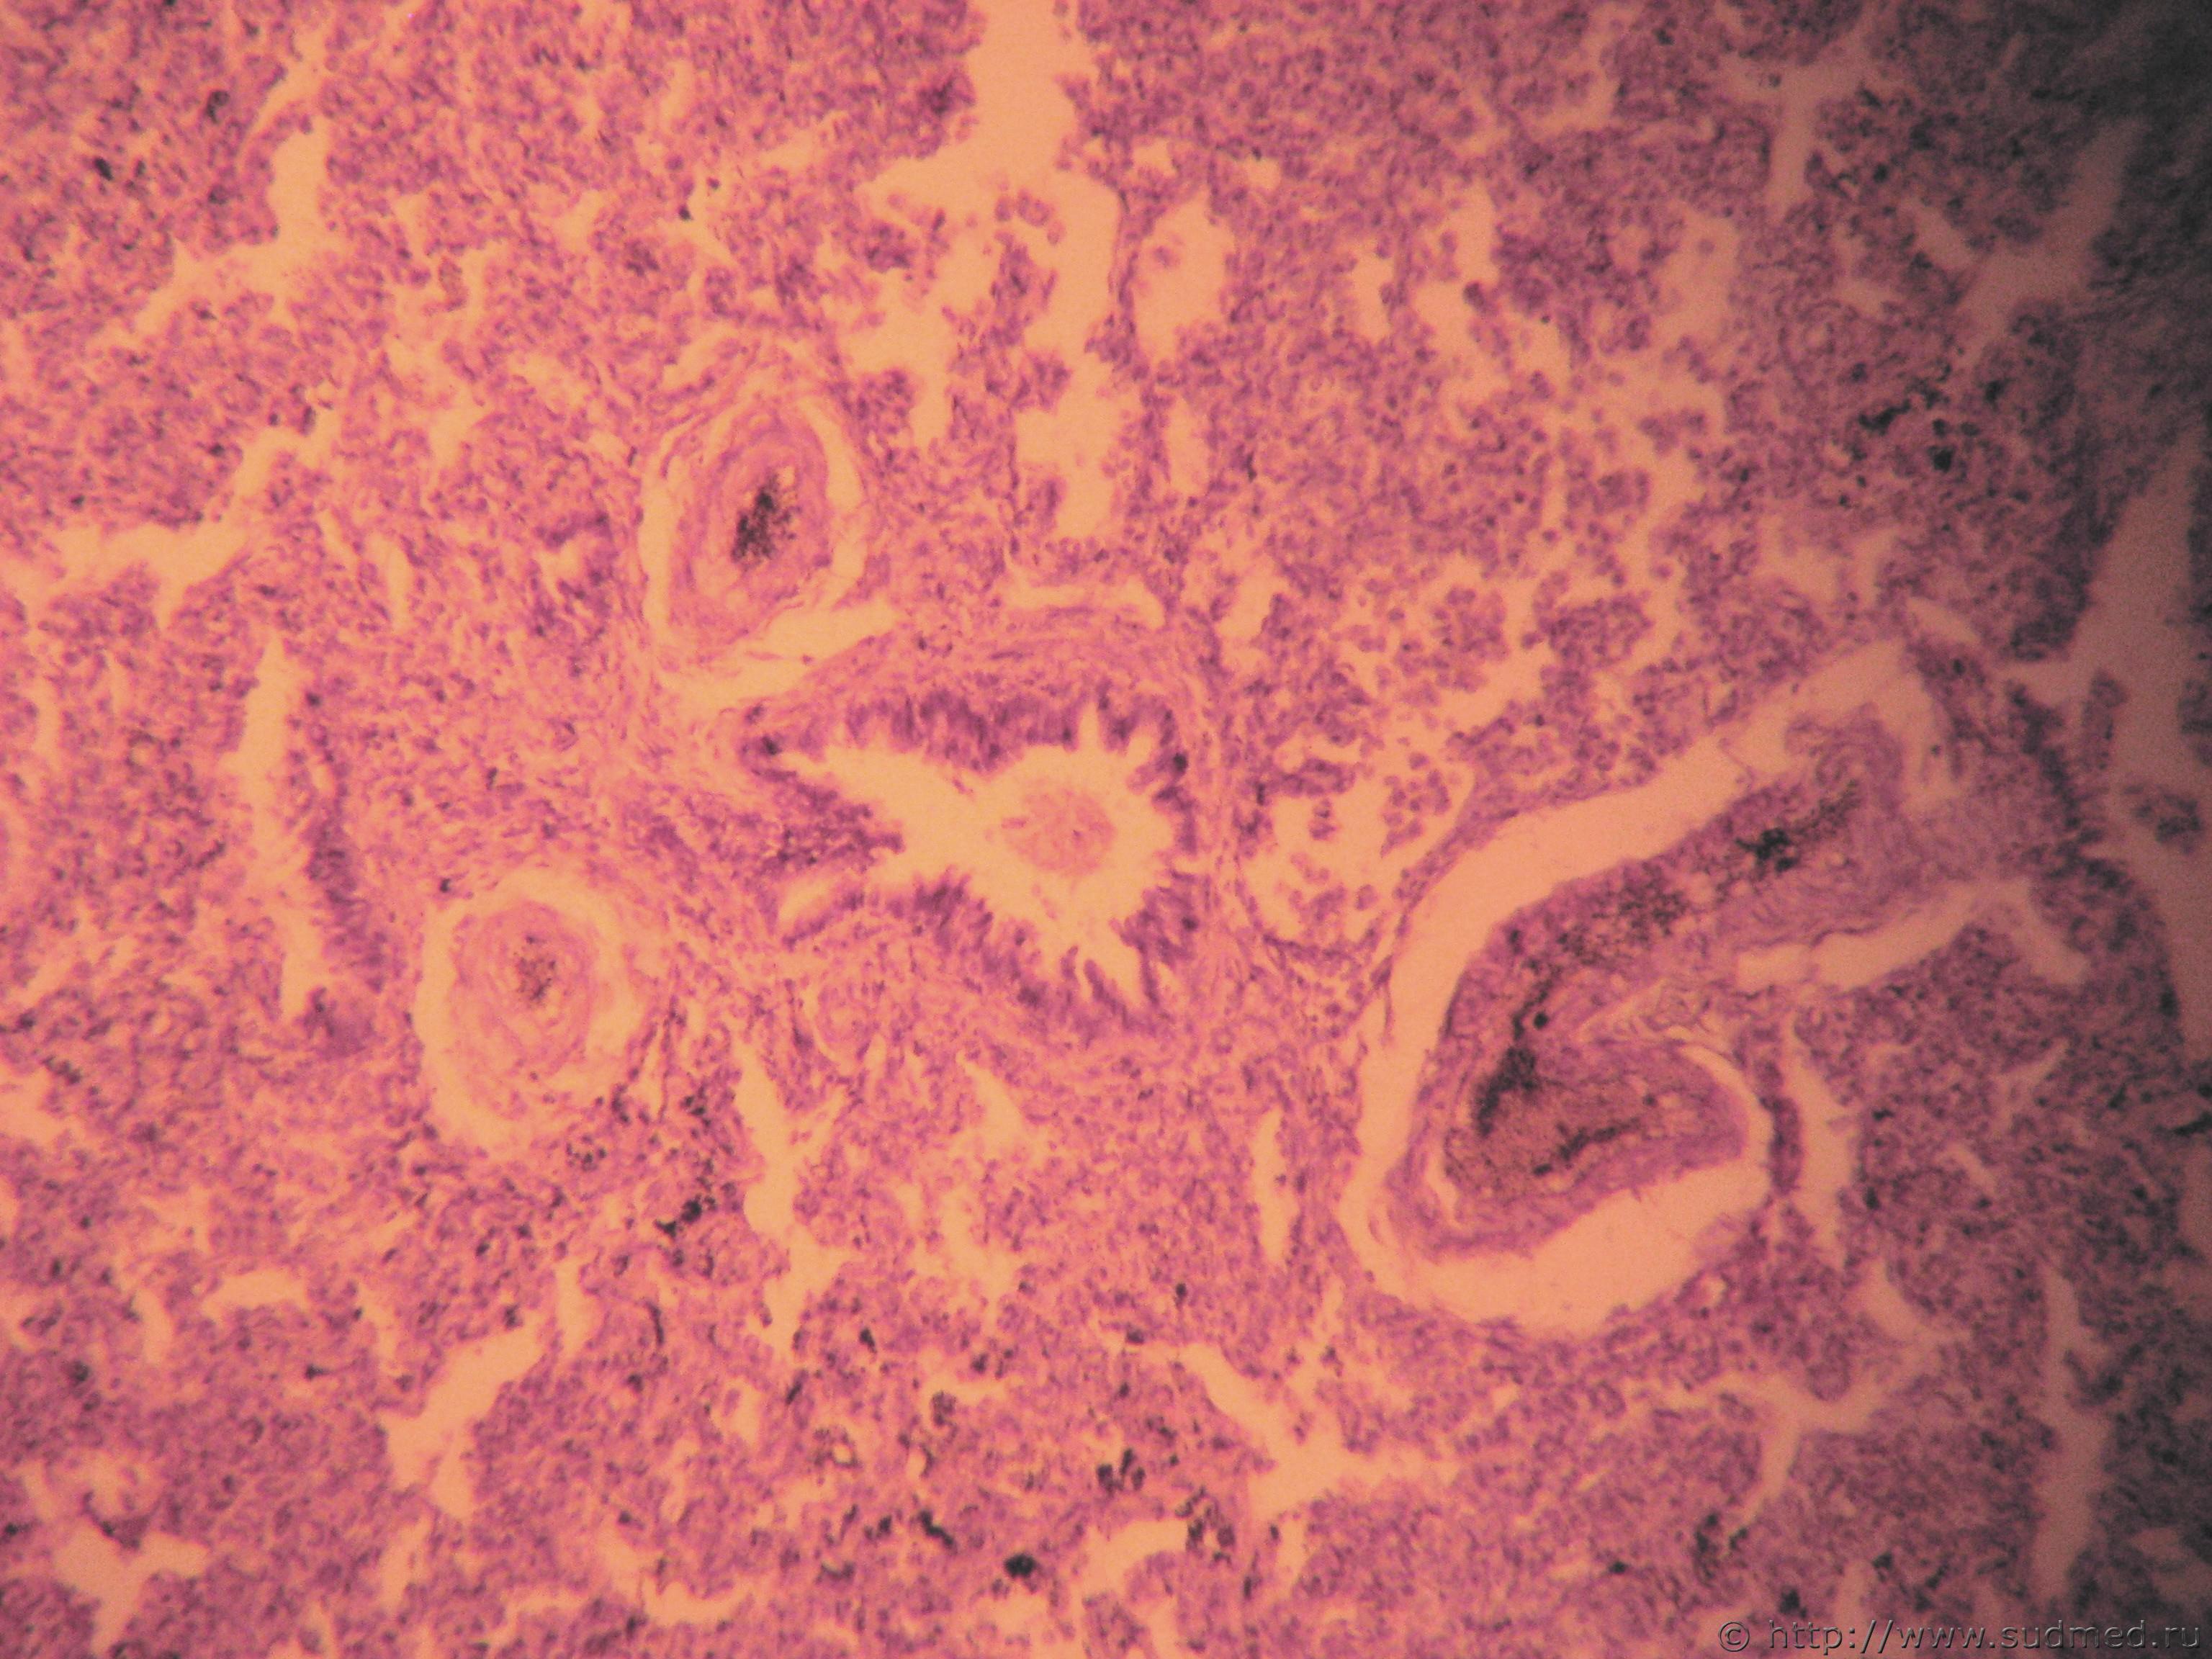

Негнойный аспергиллёз легких

Судебная медицина - Прикрепленное изображение Судебная медицина - Прикрепленное изображениеСудебная медицина - Прикрепленное изображение